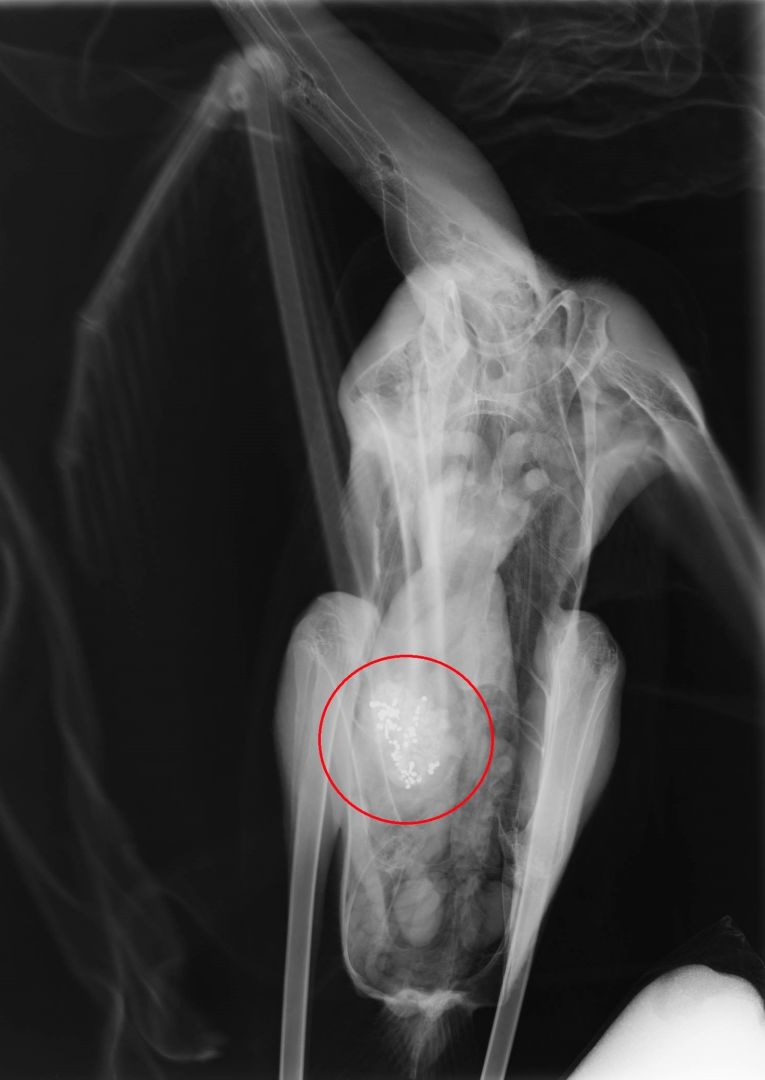

μετακινούνται μεταξύ αυτών των περιοχών για να τραφούν. Όλα τα φοινικόπτερα που

φτάσανε στις εγκαταστάσεις μας για περίθαλψη είναι με συμπτώματα μολυβδίασης,

ενώ τόσο οι νεκροψίες που έχουμε διεξάγει, όσο και οι ακτινογραφίες, δείχνουν

ότι έχουν καταπιεί σκάγια», αναφέρει η Πηνελόπη Καραγιάννη, ορνιθολόγος της

εθελοντικής οργάνωσης Δράση για την Άγρια Ζωή.